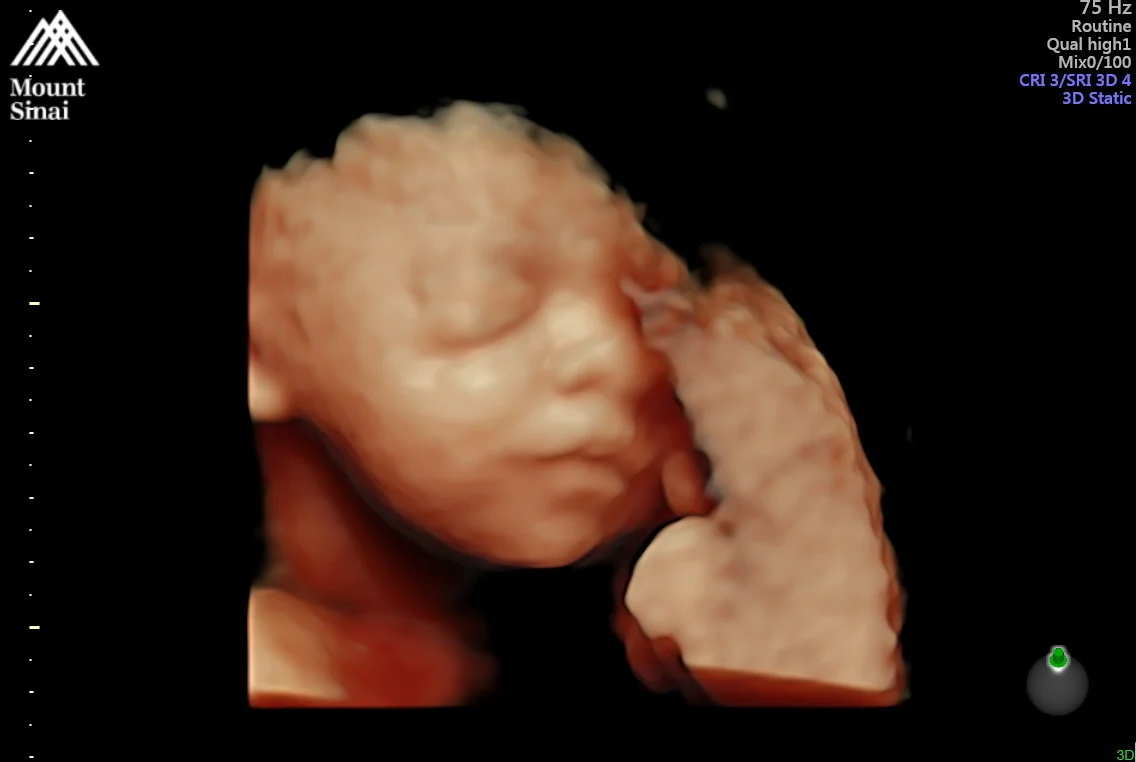

FAFA!

Twice a week, I have an ultrasound, and this is where they check Fafa’s growth, check my amniotic fluid level (which is high) and monitor the “window” where the scar from my c-section with Lucie has become compromised. Up until yesterday, the window had remained pretty unchanged from when they noticed it a few weeks ago, but now that I am in the third trimester, where there is the most growth to the baby and the uterus, the growth to the window is going to be expected and it has already started to show signs of getting longer. This is where the balancing act of how-long-can-this-window-get-before-we-need-to-deliver-the-baby is going to be crucial. Taking all other things into account, like the NSTs showing Fafa is not in distress, and that I am not having regular contractions, as well as no tension or ballooning on the window give the doctors reason to believe I am stable enough to stay on the bed rest floor, instead of the labor and delivery floor which is closer to the operating room. As the window gets longer, if all other factors remain the same, they will continue to try keep me from having to deliver for another day and then for another week. Since the window is already lengthening, we’re not sure that it will safe for me to continue through to 36 weeks, which was the original plan. But I am clinging and praying and hoping that I can get to 30 weeks, and then even 32. With each week that I am here and able to postpone having to deliver, that will be less time that Fafa will have to be in the NICU. We know that she will spend time there, so I am just very much hoping it won’t be for weeks upon weeks.